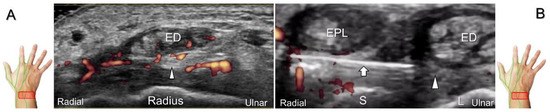

Scanning Technique

With the forearm supinated, the transducer is positioned in the axial plane at the lateral aspect of the antecubital fossa. The superficial and deep radial nerves are situated between the brachioradialis and brachialis muscles. The superficial radial nerve initially courses next to the radial artery below the brachioradialis muscle, and then departs from the radial artery in the distal third of the forearm (Figure 21A). Distally, it pierces the antebrachial fascia between the extensor carpi radialis longus and brachioradialis tendons. When tracking the terminal portion of the superficial radial nerve, the forearm can be pronated, as it courses toward the dorsal radial aspect of the wrist/hand. The superficial radial nerve travels above the proximal intersection junction between the first and second dorsal extensor compartments (Figure 21B). Later, it divides into the dorsomedial and dorsolateral branches. The former courses above the distal intersection junction of the second and third compartments (Figure 21C). The latter runs beside the extensor pollicis longus tendon (Figure 21D).

Figure 21. Sonographic imaging (short-axis view) of the superficial radial nerve from the distal third of the supinated forearm (A). With the pronated forearm, the nerve is seen to travel above the proximal intersection junction (B), divide into the dorsomedial branch coursing above the distal intersection junction (C), and the dorsolateral branch running beside the extensor pollicis longus tendon (D). Arrowheads: superficial radial nerve; white arrow: dorsomedial branch; black arrow: dorsolateral branch. RA: radial artery; APL: abductor pollicis longus tendon; EPB: extensor pollicis brevis tendon; ECRL: extensor carpi radialis longus tendon; ECRB: extensor carpi radialis brevis tendon; EPL: extensor pollicis longus tendon; C: cephalic vein.